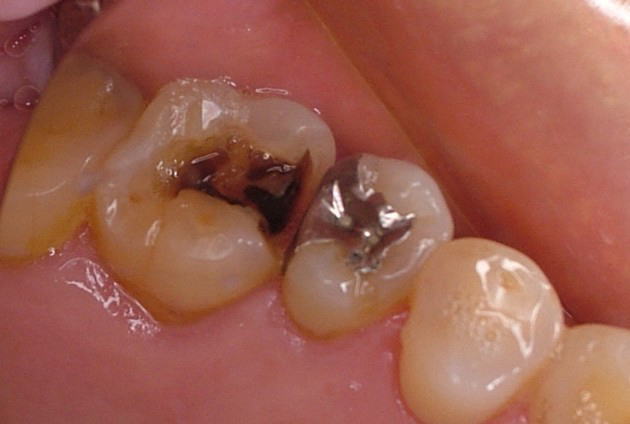

二次ウ蝕

二次う蝕では歯をたくさん削らない”補修”を考えます

二次う蝕

被せた歯やつめた歯には必ず、被せた金属と歯、つめた材料と歯の境目があります。私たち歯科医は出来る限り、この境目をぴったり合わせて隙間をつくらないように努力しています。それこそミクロンの世界で闘っています。けれどむし歯を惹き起こす細菌の身体ははるかに小さいものです。私たちの目にはぴったり適合しているように見えても細菌たちから見れば、そこにはグランドキャニオンみたいな峡谷があるに違いありません。